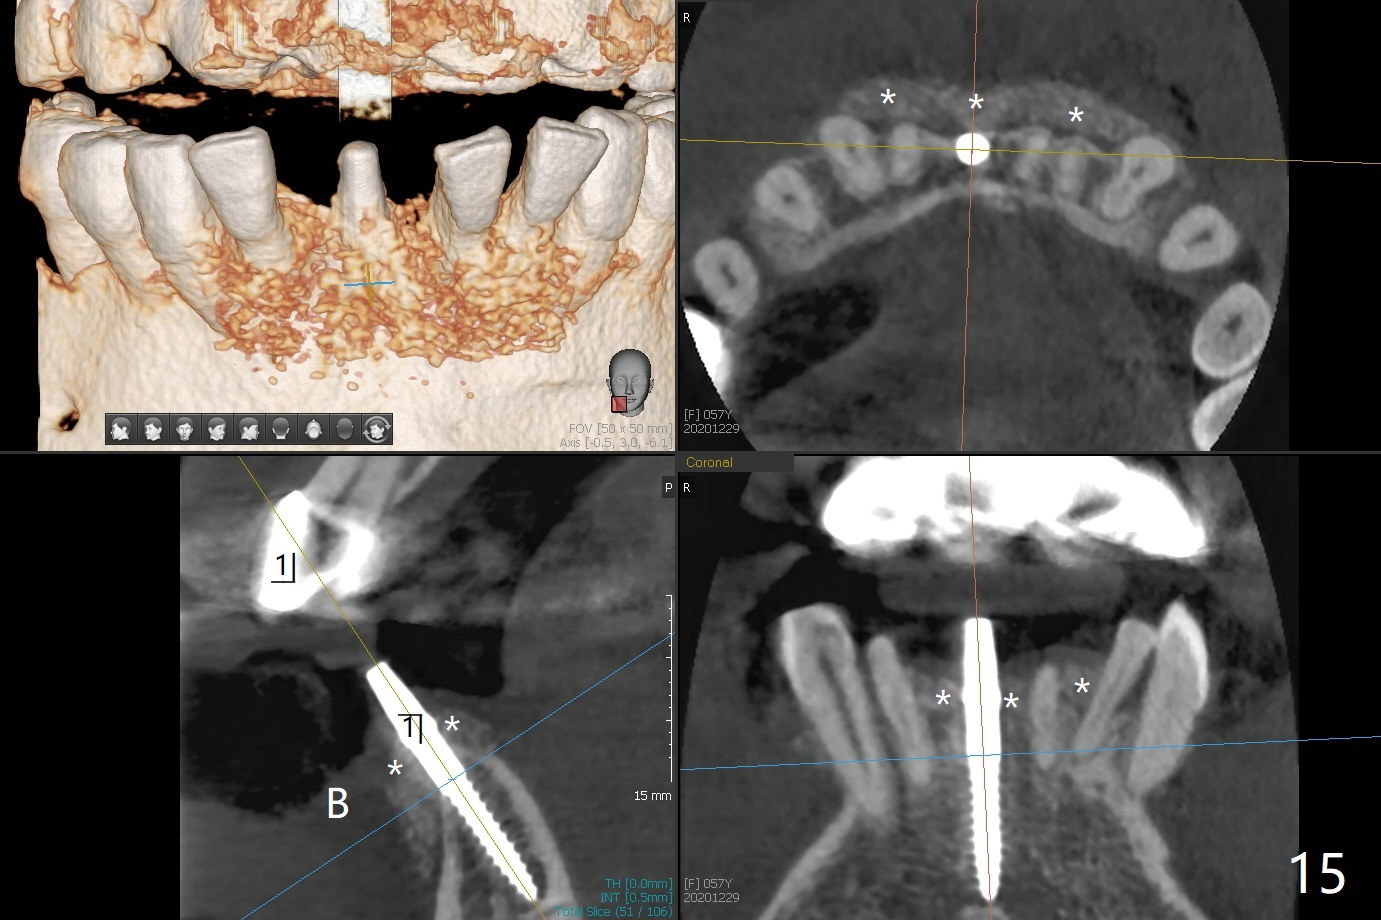

56岁女十分恐惧治疗,缺失右下1,其余切牙由于骨质吸收颊侧移位(图一:1,2),但是她不愿意拔除,同意右下1种植,牙周骨手术,植骨;植体整合后作为支抗,矫正移位下门牙。为了防止忘记舌侧瓣分离,先做舌侧切口(图二),然后颊侧瓣松弛分离(图三),包括使用前牙隧道刀(图四)切断颊侧骨膜,松弛到颊侧瓣能向舌侧牵拉3-4毫米(图五),舌侧瓣骨膜下广泛,深部分离(好像不能切断骨膜,图六),放置导板,磨平狭窄的牙槽嵴(图七:O(osteotomy)),植入2.5x12(4)毫米一段式植体(图八:故意舌侧植入,以便以后矫正),在颊侧骨板打多个出血洞(图八:箭头),然后把在平的器皿上形成的粘性骨板(sticky bone,图九),放置于植体和移位切牙周围(图十),接着使用消毒过的橡皮障punch(图十一(纸头相当于PRF膜;事先给助手示范))在三个PRF膜(图十二)打洞,套在植体和门牙上(图十三: 箭头),防止膜(图十四)和骨块(图十五,十六:*)移位,最后还必须使用最原始方法牙周敷料保护伤口(图十七)。术后9天,舌侧牙周敷料脱落,伤口稍微裂开(图十八)。术后18天撤除敷料,伤口裂开处有新鲜肉芽组织生长(图十九(*:下面是填入的骨粉,将是增宽的牙槽嵴(如果你是乐观主义者)),二十)。病人十分感激我们帮助她度过难关。她的确有sleep apnea,否定tongue thrust。术后三个月植体周围没有明显骨质吸收(图二十一至二十三),左下1,2轻度反合(图二十四),植体周围软组织健康(图二十五),5-5安置矫正器(图二十六,二十七,12 niti)。一周后下切牙向舌侧移动(图二十八),左下1,2反合纠正(图二十九)。再一周变化不大(图三十),植牙圈有些松动,两周后将重做临时牙冠,槽往舌侧移动。结果病人提前回来,植牙槽舌侧移位。一周后右下2不适(图三十一),尝试近中牵引(图三十二)。